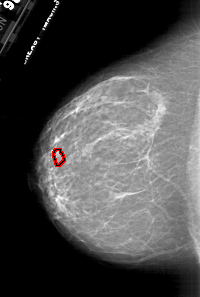

A_1787_1.LEFT_MLO

LEFT_MLO LINES 6301 PIXELS_PER_LINE 4126 BITS_PER_PIXEL 12 RESOLUTION 43.5 OVERLAY

FILE: A_1787_1.LEFT_MLO.OVERLAY

TOTAL_ABNORMALITIES 1

ABNORMALITY 1

LESION_TYPE MASS SHAPE LOBULATED MARGINS ILL_DEFINED

ASSESSMENT 4

SUBTLETY 1

PATHOLOGY BENIGN

TOTAL_OUTLINES 1

BOUNDARY